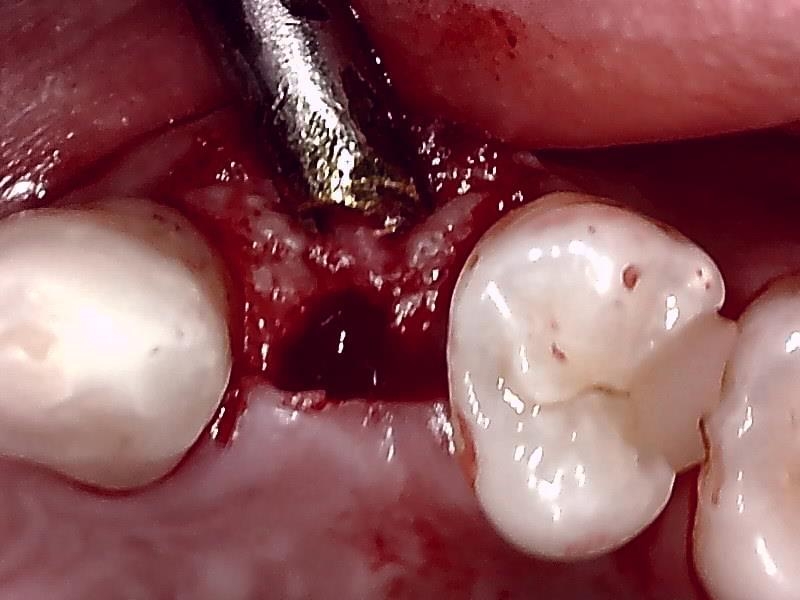

切開して歯肉剥離

ドリリング

骨造成 自家骨移植

縫合